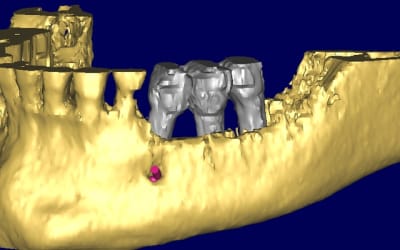

j'en viens maintenant au système FAST de Joseph.

1- les vis et la chaine titane adaptée aux vis.

(pour expliquer: ce système permet de maintenir la chaîne en l'air par sa tête.)

2-3 l'implant 35 que j'ai décidé de garder et donc de nettoyer.

4-5-6-7 sciage de la mesh titane et positionnement in situ d'un bout à l'autre de l'arcade.